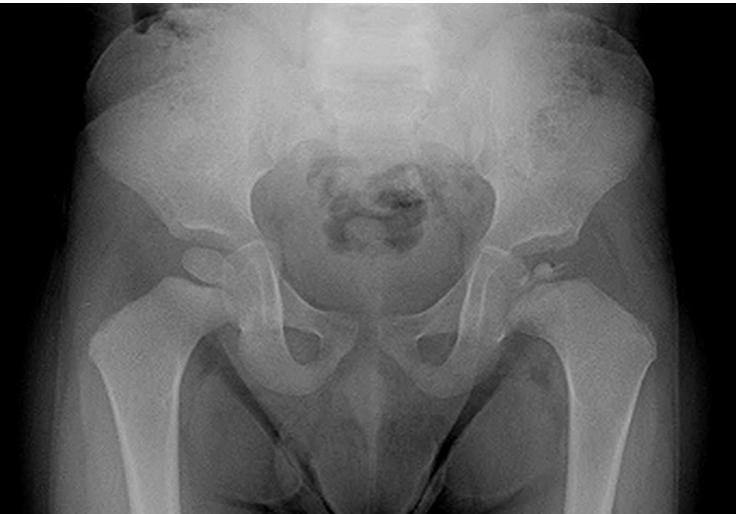

Case 1: 6-year-old, limping on left side